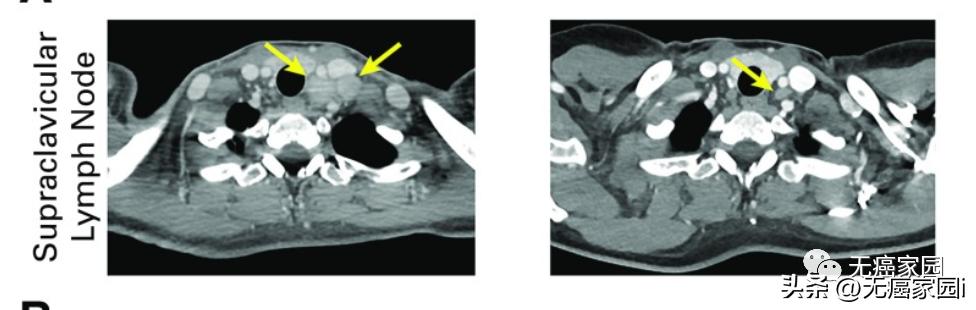

结果显示,4例患者出现不同程度的缓解。其中1例转移性宫颈癌患者接受了放射治疗和6个周期的顺铂治疗原发性宫颈癌和淋巴结转移,获得了完全缓解,肿瘤完全消失,且疗效持续超过29个月!

患者治疗前(左)和治疗后 29 个月(右)的颈部淋巴结变化